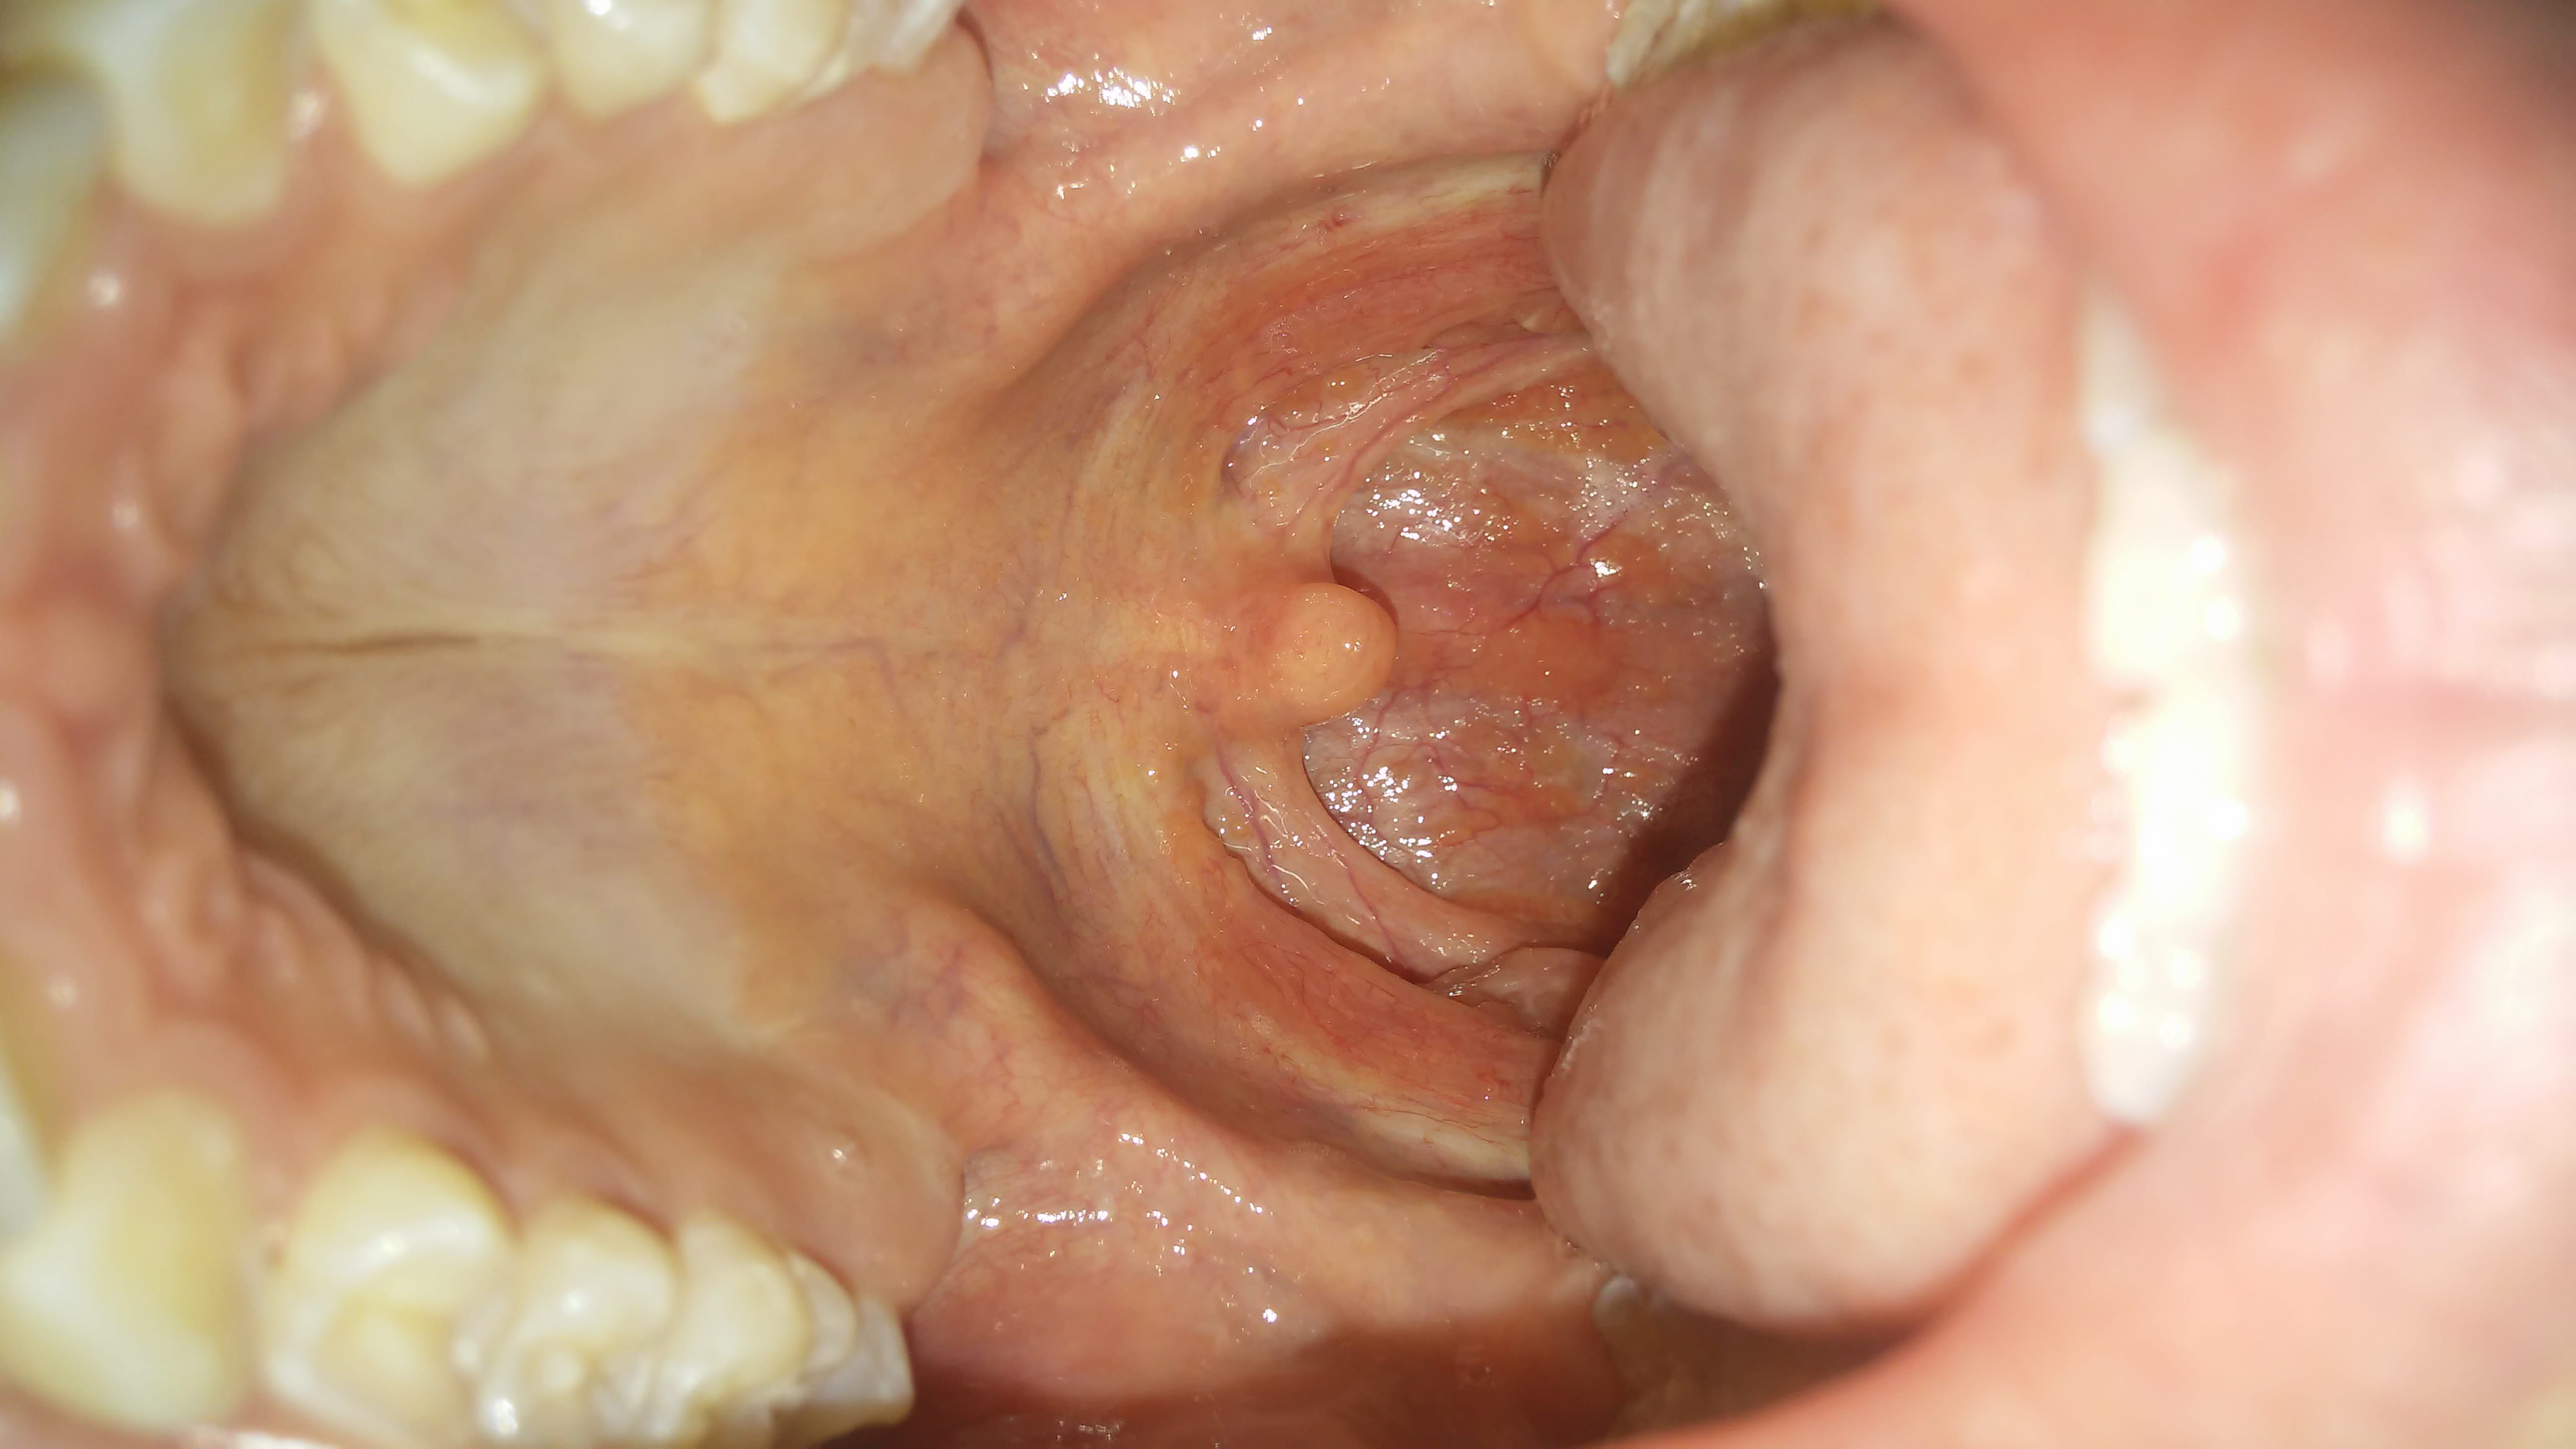

Y a día de hoy me sigue pareciendo que tengo alguna especie de virus, así que adjunto esta imagen para ver que opinan.

También creo que me afecto el paladar, como ven presenta una coloración medio amarillenta.